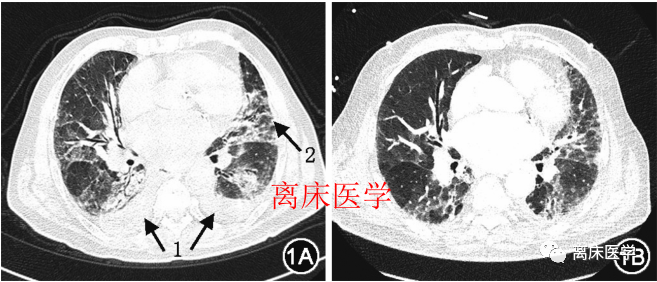

胸部CT:是肺水腫,還是新冠肺炎?應當如何最優(yōu)化處理?一、肺水腫患者肺水腫的發(fā)病機制:心力衰竭時由于肺靜脈回流受阻,肺靜脈壓力升高,導致肺部病變以滲出為主,同時,由于重力影響,此類滲出病變往往積蓄于低位,如坐位時多見于下肺,而臥位時多位于肺葉背段。此外,肺靜脈壓力的升高多導致小肺靜脈擴張,這也是心力衰竭與其他肺部感染病變的重要鑒別點。肺部感染時,肺部毛細血管充血水腫,肺泡內纖維蛋白滲出及細胞浸潤。而間質性肺炎也可見由肺門向外側伸展的磨玻璃、網格狀改變。因此,心力衰竭以靜水壓升高導致液體滲出增加,而肺炎則以炎性滲出為主。然而當兩者合并存在時情況往往變得更復雜。心源性肺水腫CT表現:早期表現為肺間質水腫,CT征象可見肺小葉間隔增厚,邊緣光滑,兩肺紋理增多,肺門影模糊,心臟增大,肺血重新分布,即上肺血管較下肺血管增粗,部分還可出現葉間裂增厚及胸腔積液。隨病情的進展,兩肺間質水腫進一步發(fā)展為肺泡性肺水腫,此時CT表現為兩肺多發(fā)磨玻璃密度及肺實變影,呈斑片狀、大片狀融合,病灶分布在兩肺野中、內帶,小葉間隔增厚往往被實變影遮蓋而顯示不清,雙側常出現少量胸腔積液及葉間裂積液,由胸膜毛細血管壓力增高所致。臨床及影像表現特點是病變動態(tài)變化快,1~2d即可出現明顯變化。肺部CT表現:間質增厚及肺泡水腫滲出,心影常常增大,合并胸腔積液也較常見(圖1A);治療后肺部病變明顯好轉(圖1B)。圖1心力衰竭患者治療前后肺部CT影像1A為治療前,可見雙肺(背段明顯)大量斑片狀及磨玻璃樣影,同時伴有胸腔積液,心影增大(箭頭1示胸腔積液,箭頭2示中央型階梯狀分布的斑片狀及磨玻璃影);1B為治療1周后,滲出病變明顯減輕,胸腔積液較前吸收,肺部病變吸收與心臟縮小、胸腔積液減少同步二、新冠肺炎患者新冠肺炎的發(fā)病機制:新型冠狀病毒屬RNA病毒,病毒通過肺泡上皮細胞的ACE2受體進入細胞,在體內誘發(fā)一系列炎性反應。主要病理改變?yōu)榧氈夤苎?、肺泡炎,肺泡腔充血明顯;不同程度的出血性肺梗死;小血管增生,血管壁增厚,管腔狹窄及微血栓形成,肺間質纖維化,肺間質局灶性炎性細胞浸潤,這也是CT上病灶呈磨玻璃密度及網格狀陰影的病理基礎。典型的CT影像學特征:包括單發(fā)磨玻璃影,多發(fā)外周帶磨玻璃影,雙肺斑片狀磨玻璃影伴節(jié)段性肺實變,雙肺彌漫性磨玻璃影伴支氣管充氣征,雙肺大面積實變影伴小葉間質增厚,同時可存在動態(tài)改變(圖2)。少數重癥患者雙肺彌漫性甚至呈“白肺”表現。圖2新型冠狀病毒肺炎患者的肺部CT影像2A示單發(fā)外帶磨玻璃樣改變;2B示雙側多發(fā)磨玻璃樣改變;2C示雙肺多發(fā)斑片樣滲出;2D示雙肺多發(fā)滲出并實變,小葉間隔明顯增厚。三、兩類患者比較示例兩類患者肺部影像均有磨玻璃影及小葉間隔增厚等特點(圖3)。圖3心力衰竭患者與COVID-19患者肺部CT影像比較箭頭所示為磨玻璃影改變。3A為心力衰竭患者的肺部CT,可見雙肺多發(fā)(左肺明顯)磨玻璃影伴小葉間隔增厚、胸腔積液;3B為COVID-19患者的肺部CT,可見左側肺明顯磨玻璃樣影伴小葉間隔增厚,胸膜下分布為主,不伴胸腔積液。3例心源性肺水腫誤診為新型冠狀病毒肺炎的影像學表現:圖1男,55歲,心源性肺水腫,既往有高血壓、糖尿病病史,有武漢疫區(qū)接觸史。圖1a,1b胸部CT見兩肺野中、內帶多發(fā)斑片狀、大片狀實變影,內可見支氣管充氣征,邊緣可見磨玻璃密度陰影,境界不清,可見雙側胸腔積液。圖1c治療后1周復查,兩肺病灶明顯吸收。圖2男,41歲,心源性肺水腫,既往體健。圖2a,2b兩肺多發(fā)磨玻璃密度病變及小葉間隔彌漫性增厚,右下肺可見胸膜下線,兩肺野外帶散在少許磨玻璃密度陰影,邊界不清。圖2c治療后1周復查,兩肺病灶吸收減少,殘留部分條索影糊。圖3男,67歲,心源性肺水腫,既往有主動脈夾層手術史。圖3a,3b胸部CT顯示兩肺多發(fā)大片狀磨玻璃密度陰影,邊界欠清,以右肺野顯著,其中右上肺病灶靠近肺野外帶胸膜下,小葉間隔增厚。兩肺門影增大,邊緣模糊,兩上肺血管較下肺血管增粗。圖3c治療后10d復查,病灶明顯吸收。四、臨床處理思維臨床上對于疑似COVID-19患者應首先予以排查,排除COVID-19后予以相應抗心力衰竭及原發(fā)心臟疾病治療即可。由于COVID-19對老年人群、有基礎疾病患者易感,目前的研究發(fā)現有高達14%~31%的COVID-19患者合并高血壓等心血管疾病。因此對于確診COVID-19合并心力衰竭患者,應當進行最優(yōu)化處理。疫情防控期間,以下心血管急危重癥可以考慮收入院,并采取優(yōu)化藥物治療,以便緩解患者病情,為后續(xù)進一步治療贏得時間和機會。1.具有溶栓適應證的急性ST段抬高型心肌梗死(STEMI)建議溶栓,首選第3代溶栓劑。2.超過血運重建時間窗,但仍有嚴重胸痛、心電圖ST段抬高或機械性并發(fā)癥等嚴重并發(fā)癥的急性STEMI患者。3.高危(GRACE評分≥140分)非ST段抬高型心肌梗死(NSTEMI)及不穩(wěn)定性心絞痛患者。4.非復雜型StanfordB型夾層患者(A型建議收外科治療)。5.急性肺栓塞患者。6.急性心力衰竭患者。7.高血壓急癥患者。